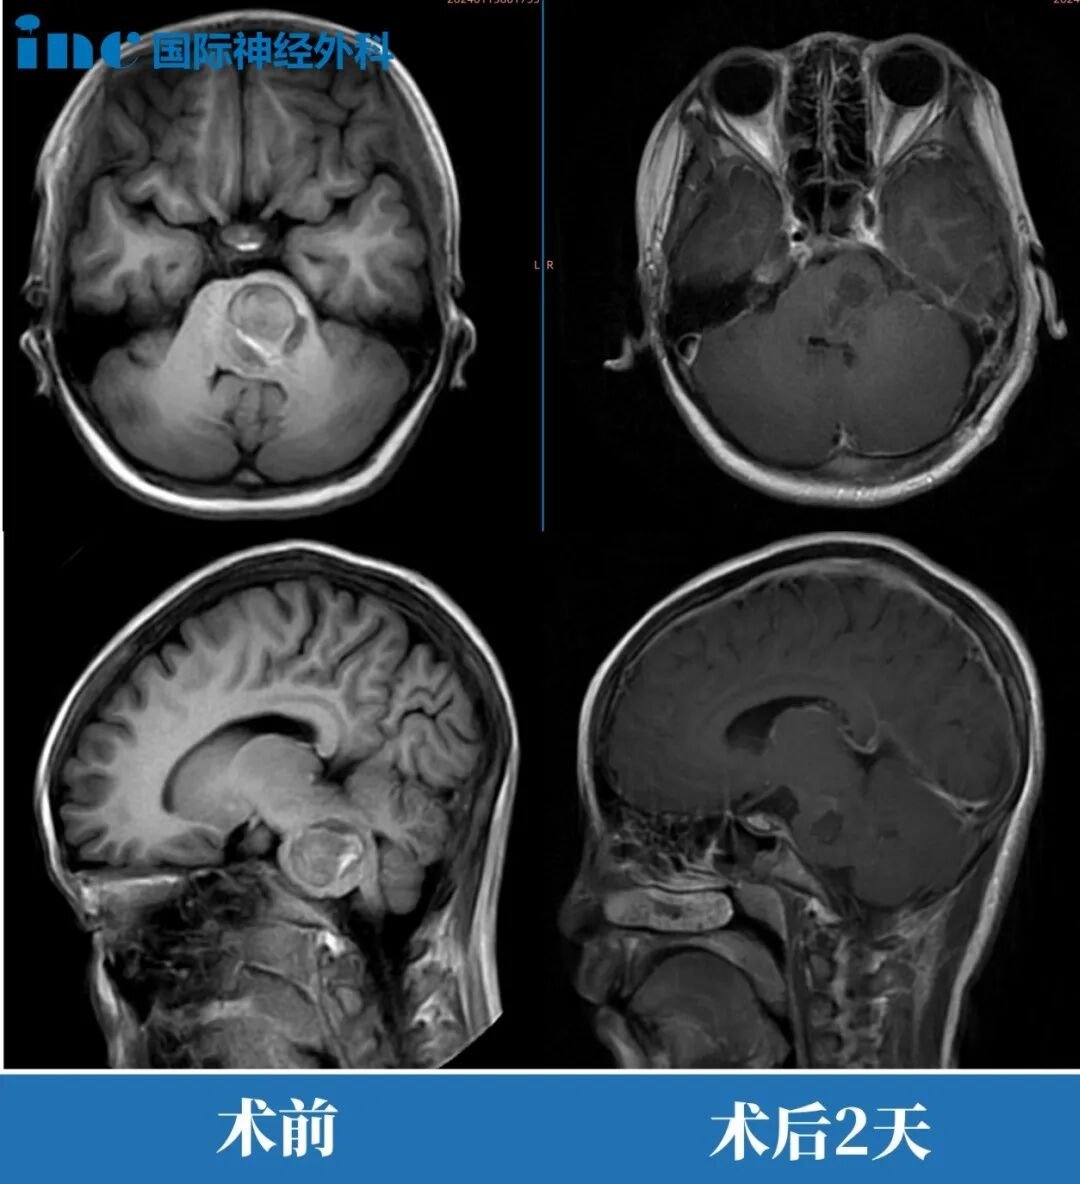

原本计划在ICU观察2天的小晴,提前1天被转回普通病房,此时的她肢体活动均如常,已能正常进食,精神状态恢复良好。术后2个月,小晴早已回归校园,随访时巴教授表示:“片子非常好,脑干形态已经恢复正常。”

案例来源:巴教授2024年国内示范手术